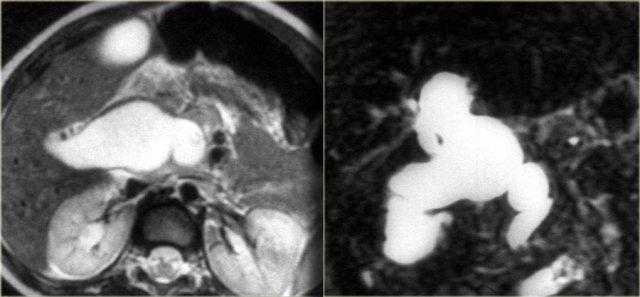

Bên trái là hình ảnh MRCP của một bệnh nhân mắc PSC.

Lưu ý chỗ hẹp lớn, rất đáng lo ngại cho ung thư đường mật (mũi tên).

Các chỗ hẹp trong PSC thường có sự chuyển tiếp đột ngột, trong khi ở đây chúng ta thấy hình ảnh “vai” (shouldering), gợi ý hiệu ứng khối.

Ngoài ra, có giãn đường mật trong gan ở phía thượng lưu vùng hẹp này.

Bên trái là hình ảnh MRCP của một bệnh nhân cho thấy chỗ hẹp ở mức rốn gan.

Trên MRCP, chỗ hẹp này trông dài và đáng lo ngại cho ung thư đường mật.

Tuy nhiên, trên ERCP, các ống mật đã được bơm căng bằng thuốc cản quang và chúng ta có thể thấy đây là một chỗ hẹp ngắn, phù hợp với chẩn đoán PSC.

Trong quá trình theo dõi, trường hợp này được xác nhận chỉ là PSC.